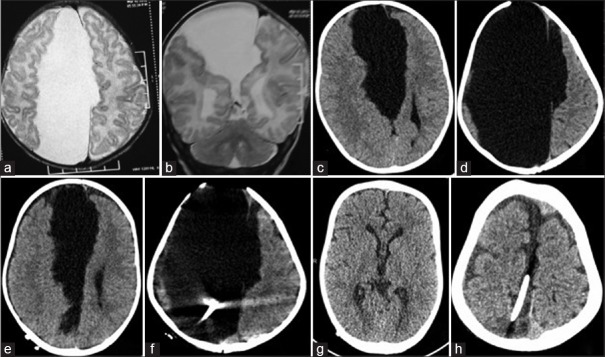

Figure 3.

Preoperative images of a 14-month-old child demonstrating T2-weighted axial magnetic resonance imaging (a), T2-weighted coronal magnetic resonance imaging (b) and axial computed tomography (c and d) views of a large frontoparietal Barkovich Type 2a interhemispheric arachnoid cyst with agenesis of corpus callosum. He underwent right low pressure cystoperitoneal shunt. Postoperative day 1, axial computed tomography (e and f) showing catheter inside the cyst. Postoperative axial computed tomography at 18 months follow-up showing marked resolution of cyst volume and hydrocephalus